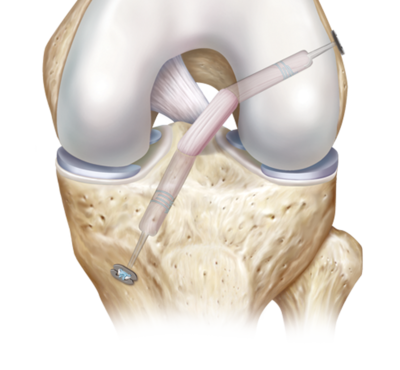

The most commonly injured ligament around the knee that requires surgical intervention is the anterior cruciate ligament (ACL). A typical mechanism of injury for tearing this structure is a non-cont..